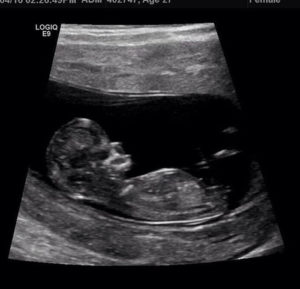

Alex und Zoe konnten ihre letzte Reihe von Schock vollständig überwinden, als sie eine weitere gute Nachricht erhielten. Ja, Zoe erwartete wieder und Alex würde alles auf der Welt tun, um sein gesundes Baby in seinen Armen zu halten. Aufgrund ihrer bitteren früheren Erfahrungen hatten sie Angst genug, um diesmal zumindest bis in die ersten Monate der Schwangerschaften ein Geheimnis zu halten, entschieden sie sich, niemandem davon zu erzählen.

Glücklichere Nachrichten.

So sagte Zoe einmal: "Ich schätze und lieben und lieben [Garner] mehr als ich kann ausdrücken und ich kann es kaum erwarten, unser erstes Kind bald zu treffen." Sie brachen endlich die Nachrichten aus, nachdem die Ärzte ihnen versicherten, dass es in der Schwangerschaft keine Komplikationen in der Schwangerschaft gibt. Es klang leicht, obwohl es nicht so ist, wie es sein würde.

Die Lieferkomplikation

Es war im Monat November 2016, dass Zoe ihre Arbeit hatte. Die Lieferung hatte eine wichtige Komplikation, als die Ärzte Zoe und Alex über den Zustand der Nabelschnur des Babys informierten. Es wurde zweimal um den ungeborenen Hals eingewickelt, und der Griff würde enger werden, wenn das Baby herauskommt. Das entsetzte Paar könnte nichts tun, als beten, dass sie ungeboren ist, um in Ordnung zu sein.

Warten auf Baby zum Weinen